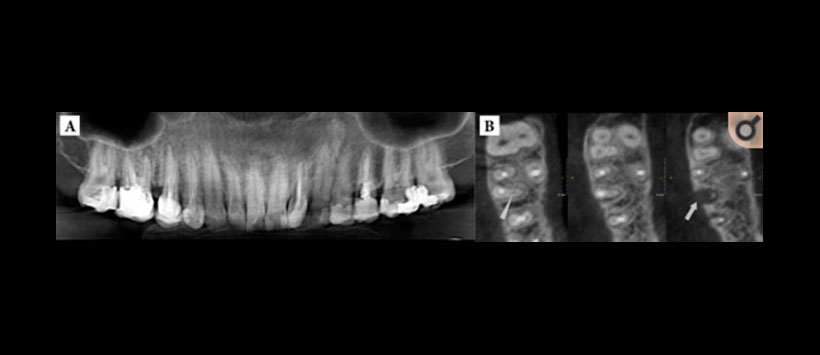

- Periodontitis apical – Figura 1